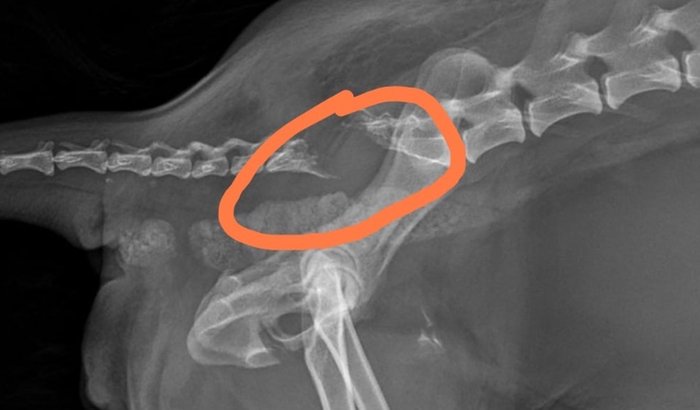

Laika fugiu e acabou sendo atropelada, com isso fraturou a cauda sendo nescessario cirugia para amputação . ver tudo

Laika fugiu e acabou sendo atropelada, com isso fraturou a cauda sendo nescessario cirugia para amputação .